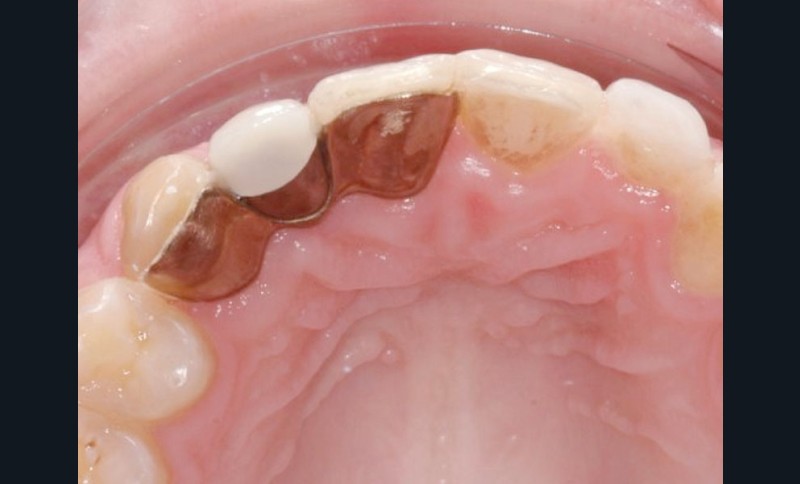

Des problèmes esthétiques liés à l’implantation chez le jeune adulte

L’implant se comporte logiquement comme une dent ankylosée. Il s’ostéointègre dans l’os qui continue à se modeler tout en étant transporté par la croissance des os voisins [1]. Cette croissance faciale se poursuit après l’âge adulte et s’arrêterait…